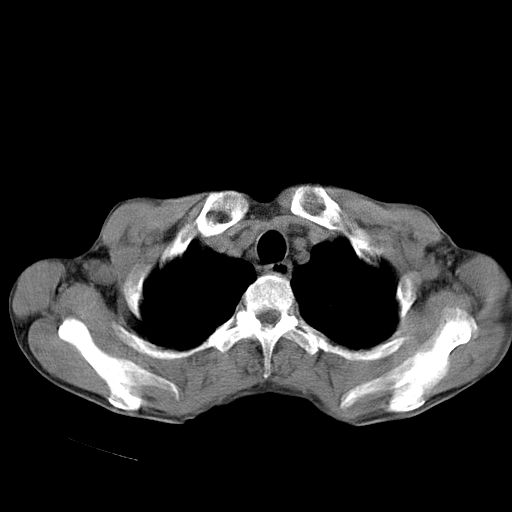

以下是引用苯小孩在2007-5-24 12:47:00的发言:[br]右侧肺门处不均匀密度软组织块影,远端肺组织见斑片模糊影,纵隔内淋巴结明显肿大,边界不清.<纵隔窗第12层面支气管内似见软组织结节>[br]考虑:1、右侧中央性肺癌并阻塞性肺炎并纵隔淋巴结转移可能性大.建议强化或纤支镜进一步检查.[br]2、隆突下淋巴结肿大/食道病变?请做鉴别检查.

以下是引用jw-830在2007-5-24 15:24:00的发言:[br][br] [br] 考虑右肺中央型肺癌并阻塞性炎症,右肺门及纵隔淋巴结转移。 [br] [br][br]